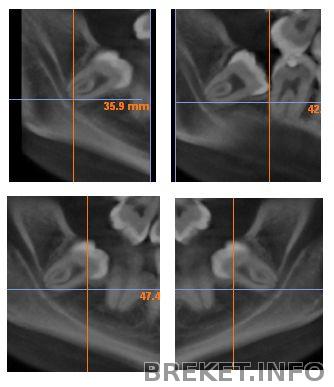

Вот, нашла фотки с томограммы, видно что корни прям чуть ли не в нерве...

А это верхняя, сейчас она ещё больше в 7ке...